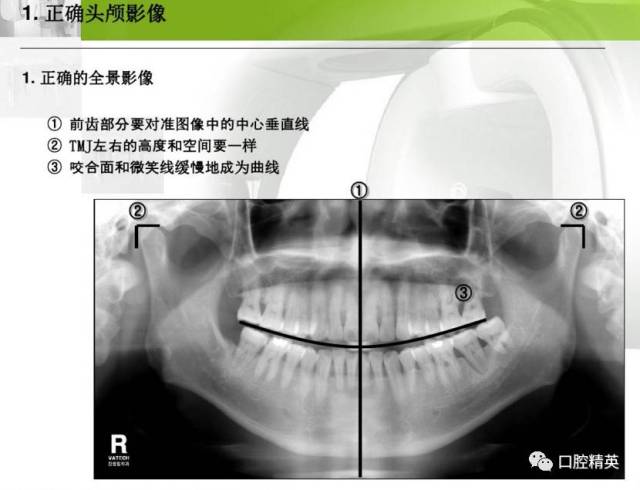

小牙片的正确拍摄方法,小牙片拍摄技巧图解

【实用技巧】口腔牙片拍摄技巧

牙片机拍摄程序定位

小牙片拍摄技巧图解

牙片拍摄技巧图解